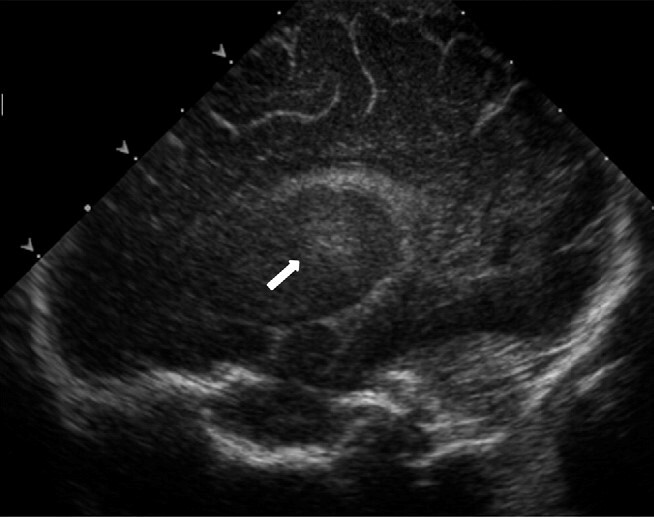

Neonatology Increased Thalamic Echogenicity Image